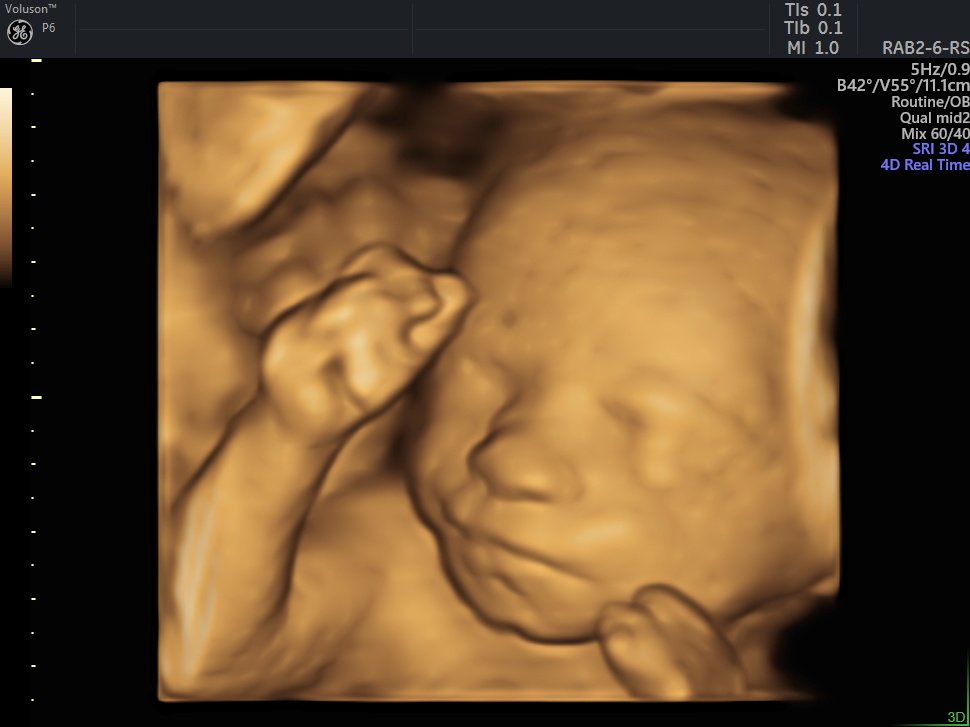

4 Boyutlu (Renkli) Ultrason ve Doppler Ultrasonografi

4 D Ultrasonografi